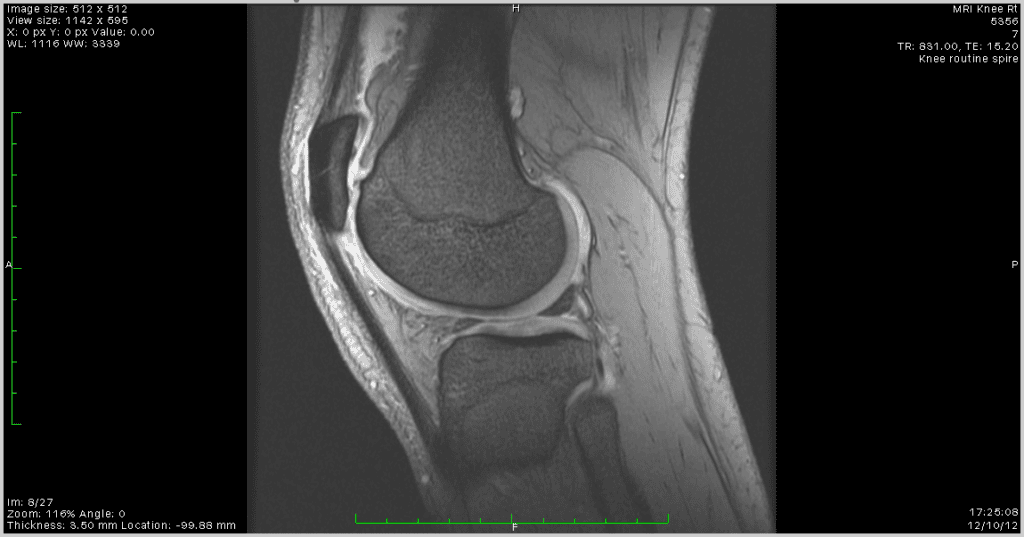

It seized several times during the walk — a grinding reluctance from a joint that has been carrying too much weight for too long. This is not new. I have been warned that arthritis may be developing in both knees. An MRI of my right knee from 2012 showed early structural changes consistent with excess load over time. I have included that scan here not for drama but for context: this is what carrying 101 kilograms looks like from the inside, a decade and a half of it.

Every kilogram I lose between now and Day 30 is a kilogram that knee no longer has to support. The target of 88 kilograms is not an aesthetic goal. It is a medical one.